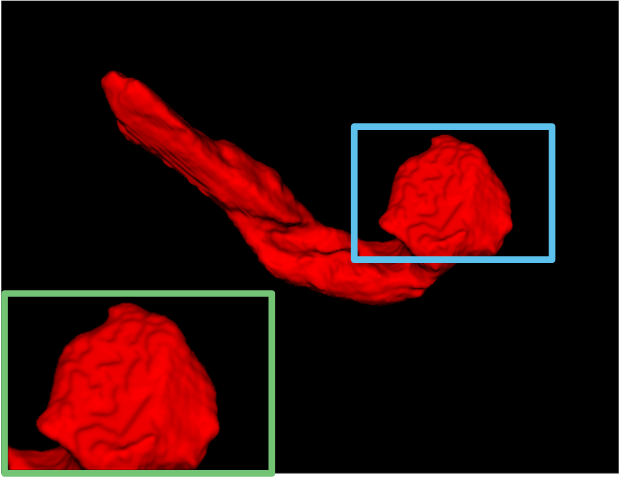

4.4 Result on Pancreas-CT Dataset

Table 2 shows the results specific to Pancreas-CT. Note that the volumes in this dataset provide a more complex backdrop compared to LA MRIs, rendering pancreas segmentation a more challenging task. To facilitate an intuitive comparison, we again employ several state-of-the-art competitors, namely UA-MT [42], SASSNet [17], DTC [20], MC-Net+ [37], RCPS [45], and CauSSL [22]. The performance metrics reported in their respective papers are directly adopted. Similarly, we employ Vnet with varying proportions of labeled data (10%, and 20%) for comparative analysis. Similarly, we select 6 samples for 10% supervision and 12 samples for 20% supervision from the training dataset, and consider the remainder as unlabeled data.

Yet within a notably challenging task, the proposed DCF demonstrates promising performance in both scenarios. Even with only 10% of the data labeled, DCF significantly improves Dice scores from 55.10% to 78.94%, surpassing all other SSL methods. With 20% labeled data, DCF achieves a Dice score of 81.65%, outperforming again other cutting-edge competitors. It should be noted that our proposal exhibits the smallest disparity between 10% and 20% labeled scenarios, as illustrated in Figure 4. The marginal 2.71% variance in DCF’s Dice scores between these proportions suggests its effective utilization of unlabeled data, thereby demonstrating robustness and generalization capabilities. We further deliver visualization of the results obtained by DCF and others, as illustrated in Figure 6. It is observed that our results closely resemble the ground truth (GT) compared to those of other methods. Moreover, our method exhibits more precise boundary positioning and provides the more detailed information.